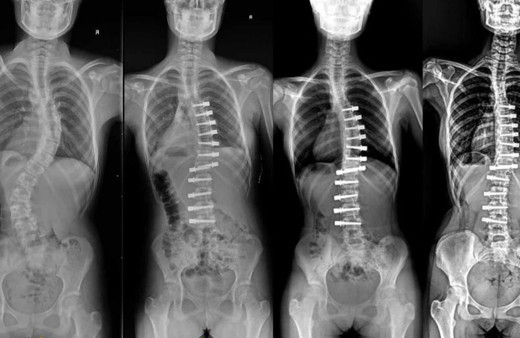

Vida